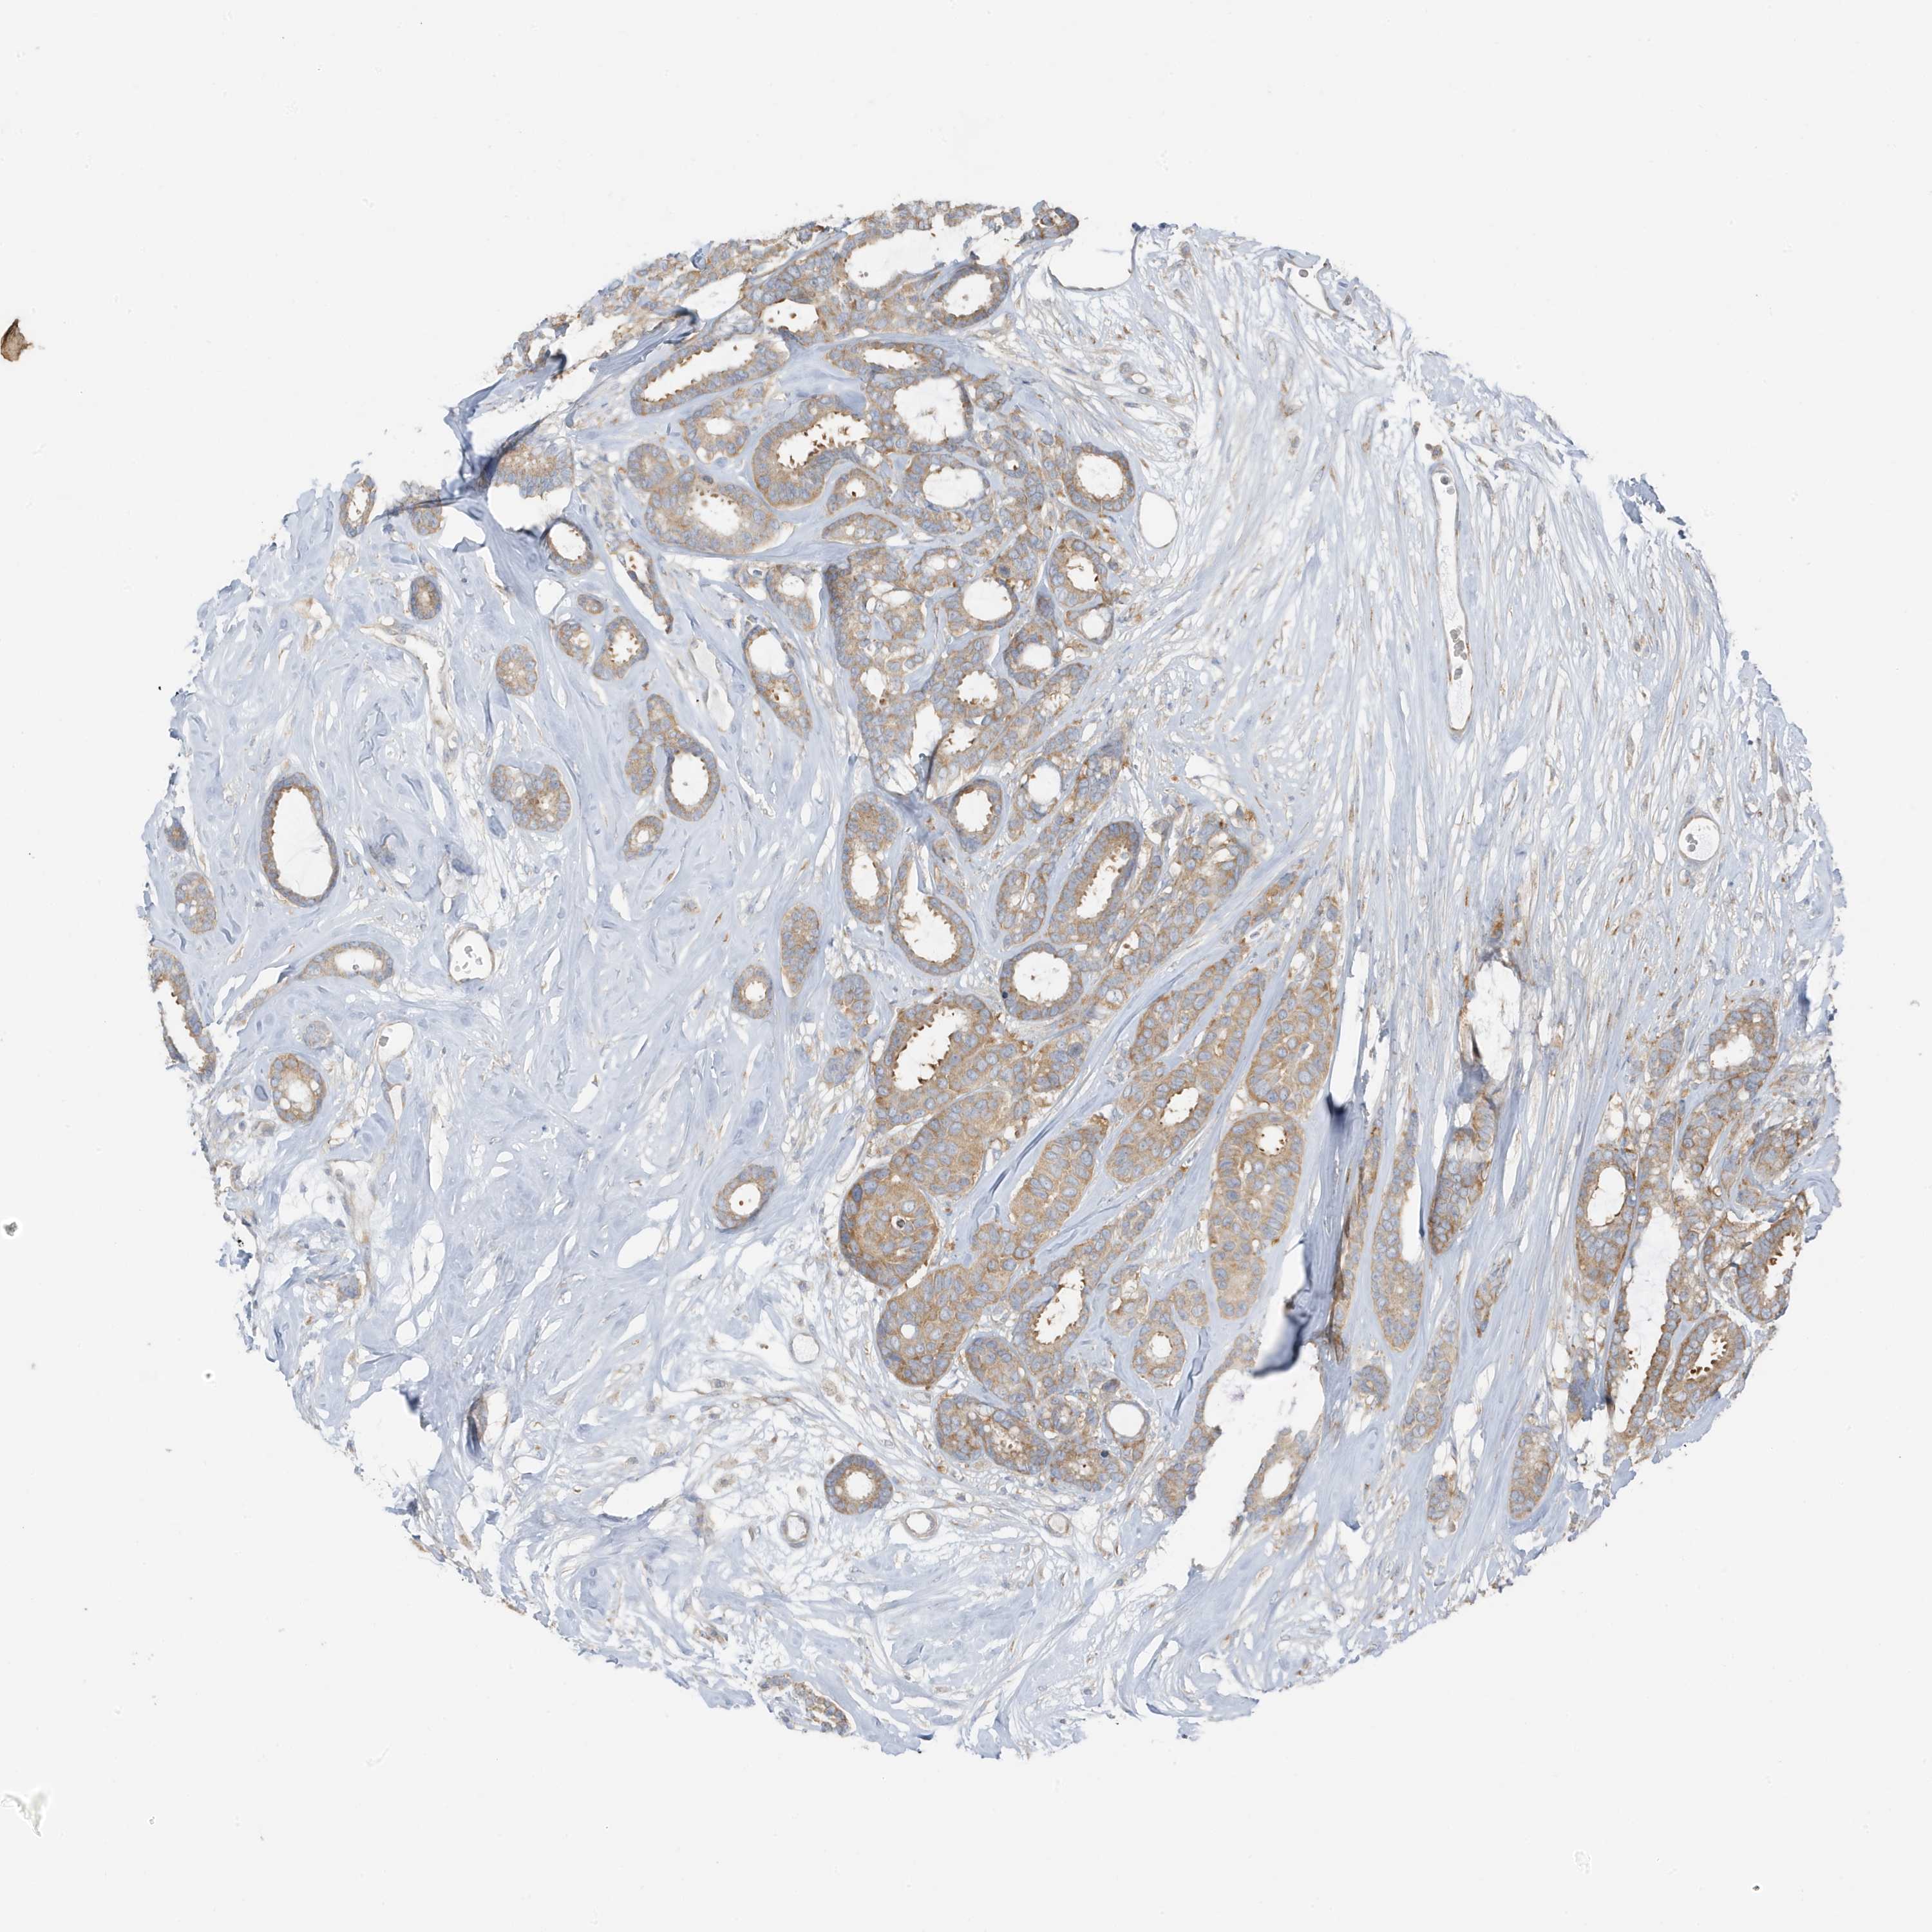

CANCER BREAST CANCER Show tissue menu

BRCA TCGA BRCA VALIDATION PROTEIN EXPRESSION